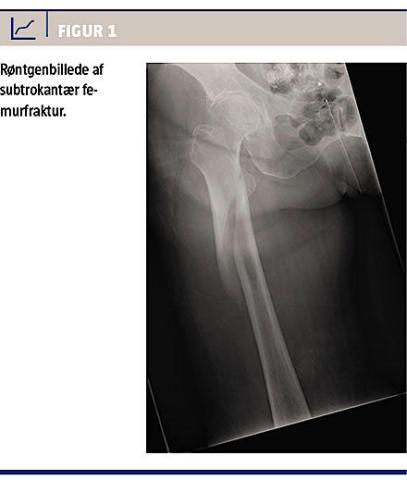

En 82-årig kvinde blev indbragt med en subtrokantær femurfraktur (Figur 1). Hun var afkølet (temperatur 31,5 °C) og havde myoglobinuri (myoglobinniveau 12.000 mikrogram/l (< 61)). Hun havde en enkelt kaffegrumslignende opkastning ved ankomsten til skadestuen. Hendes tilstand blev vurderet af en organkirurg, der ikke fandt indikation for yderligere

intervention. Hun var i behandling med dabigatranetexilat pga. atrieflimren. Blodprøver ved ankomsten viste følgende værdier med referenceværdier i parentes: hæmoglobin 6,6 mmol/l, APTT 83 s (27-40 s), koagulationsfaktor II + VII + X 0,48 arb.enh./l

(0,7-1,3 arb.enh./l), karbamid 15,7 mmol/l (3,1-7,9 mmol/l), kreatinin 178 mikromol/l (45-90 mikro-mol/l), glomerulær filtrationsrate 24 ml/min (> 60 ml/min). I løbet af dagen blev hun varmet op; hun blev senere på dagen vurderet som stabil og operabel og blev med normal temperatur kørt til operation 15 timer efter ankomsten. Under operationen var det vanskeligt at reponere frakturen tilfredsstillende, og den komminutte subtrokantære femurfraktur blev osteosynteret med langt marvsøm og cerklage. Under indgrebet var der konstant sivning fra alle overflader pga. svær koagulopati. Trods intensiv kirurgisk hæmostase var der et peroperativt blodtab på 6.000 ml. Patienten fik erstattet tabet i henhold til hospitalets retningslinjer for blodtransfusion ved stort blodtab. Efter endt operation blev hun overflyttet til en intensivafdeling, hvor hun døde dagen efter af multiorgansvigt.